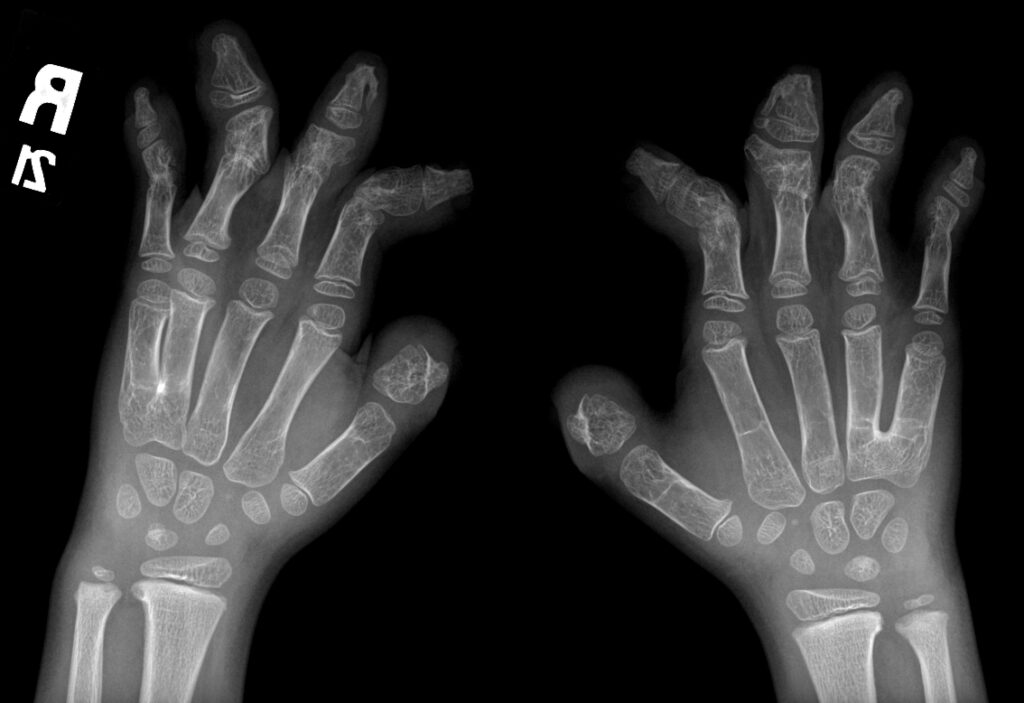

- Deformidades en las manos y pies: Incluyendo sindactilia, donde los dedos están fusionados.

El diagnóstico del Síndrome de Apert se basa en un examen físico detallado, radiografías y pruebas genéticas para identificar la mutación en el gen FGFR2. El tratamiento implica cirugía para corregir craneosinostosis y deformidades en manos y pies. Es crucial la intervención de equipos médicos multidisciplinarios especializados en cirugía craneofacial y genética.